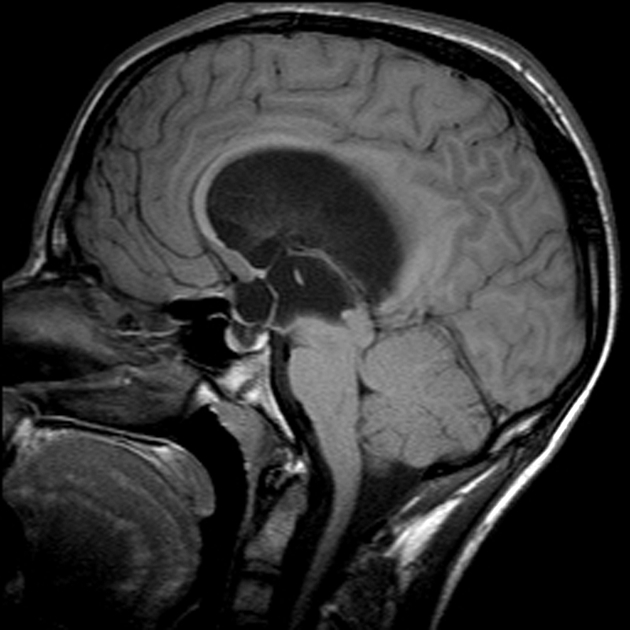

What is the key imaging fx of a pilocytic astrocytoma?

About 66% are cystlike with an enhancing mural nodule.